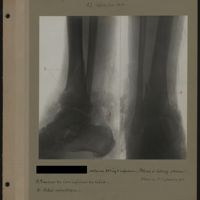

0033 - Page 29 - [Radiographies de la cheville, du tibia et de la fibula]0033 - Page 29 - [Radiographies de la cheville, du tibia et de la fibula]

0035 - Page 31 - [Radiographies de la cheville, du tibia et de la fibula]0035 - Page 31 - [Radiographies de la cheville, du tibia et de la fibula]